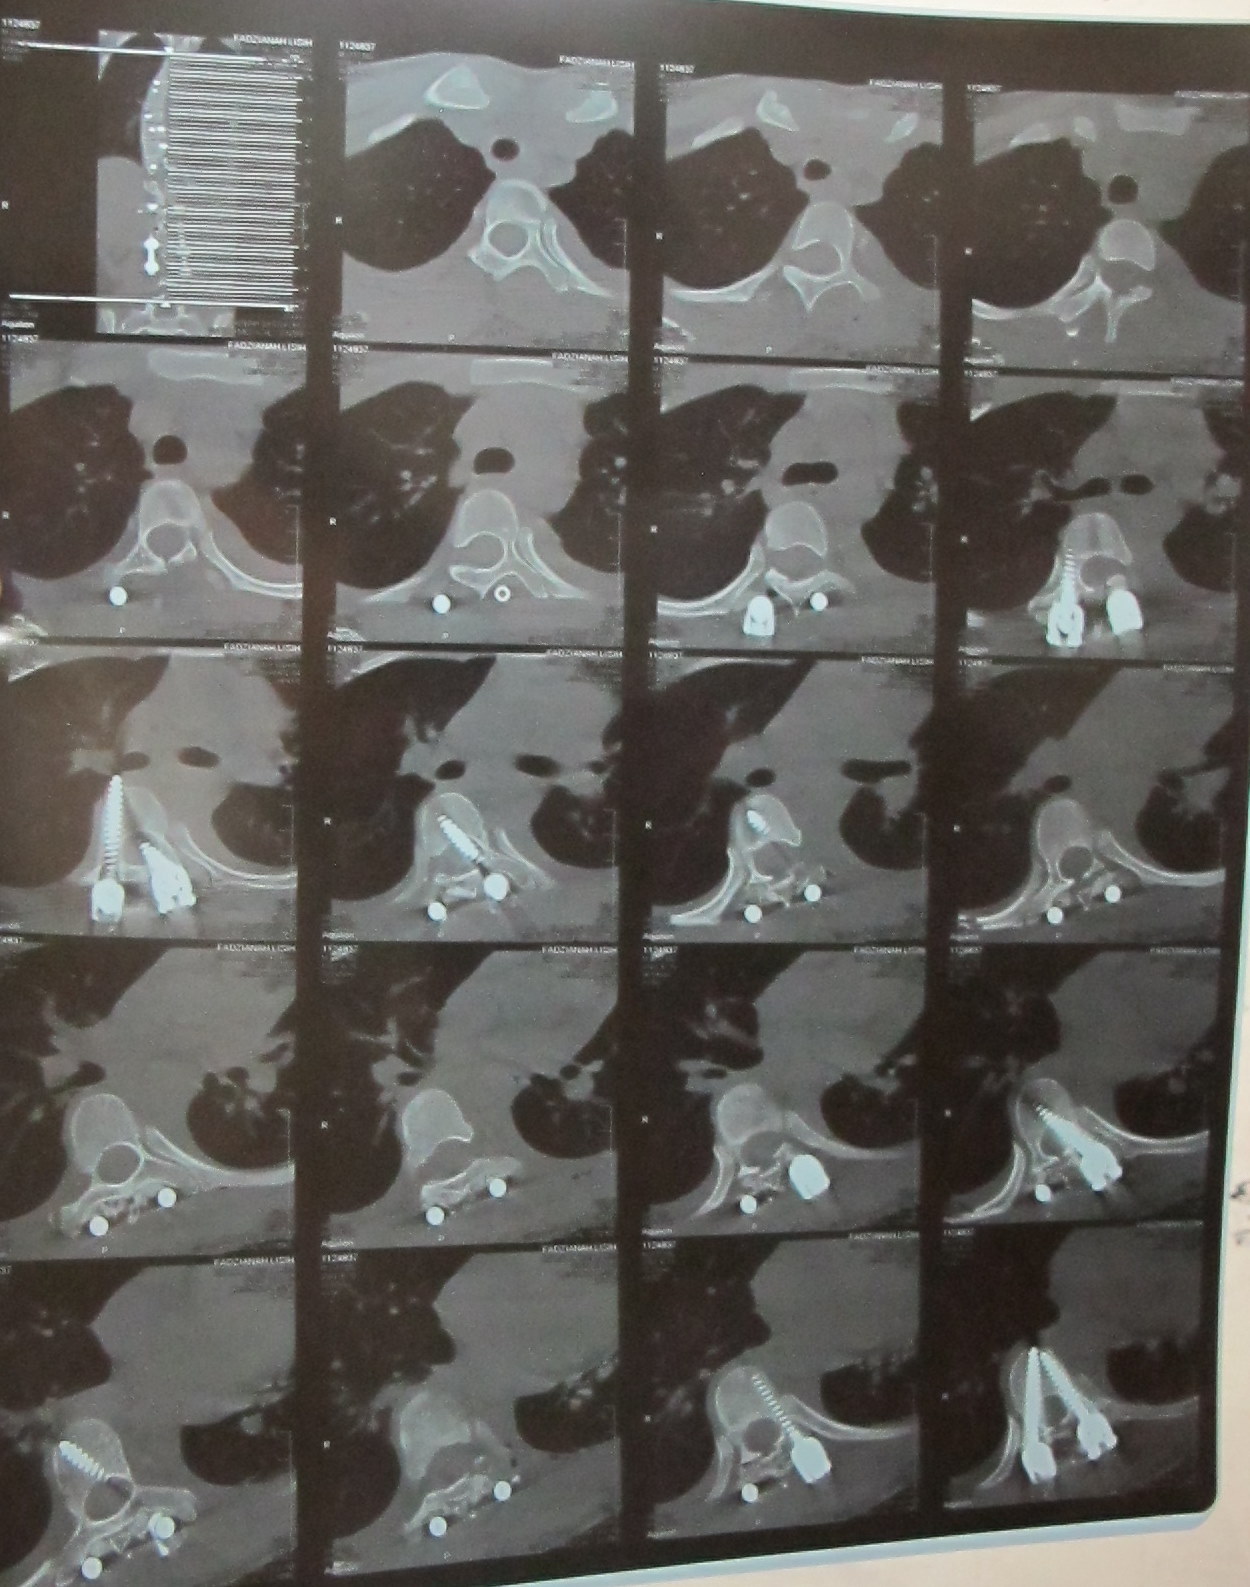

MRI Scan

kira-kira jam 11 pagi, doktor pakar Fadz, (Dr.Chuah) datang dan kata,  ada satu skru(paling atas kiri) yang ada dalam spine Fadz, telah mengenai saraf kaki kiri Fadz...itulah punca kaki kiri Fadz tak boleh gerak...Dr. Chuah kata lagi, Fadz kena buat pembedahan kali kedua supaya mereka boleh melonggarkan skru dan supaya Fadz boleh gerakkan kaki lagi...Fadz boleh rasa sebak dan rasa hati  Fadz HANCUR sebab keadaan Fadz macam tu...